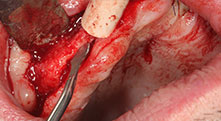

Potrebbe descrivere in breve, ad esempio, la procedura che utilizza per fare spazio ai blocchi ossei per il trapianto?

Bratu: Preferiamo prelevare l'osso dalla cresta esterna obliqua della mandibola posteriore, non dalla regione interforaminale. Dopo l'incisione del tessuto molle, utilizziamo le nuove seghe ossee per definire la quantità di osso da prelevare. Quasi nell'80% dei casi adottiamo lo stesso approccio, quindi utilizziamo le seghe ossee, anche per l'intera preparazione. Potremmo utilizzare anche altri strumenti piezochirurgici e, al termine, un bisturi per far spazio al blocco. Secondo noi, si tratta di una tecnica chirurgica molto efficace.

Potrebbe spiegarci alcune altre tecniche che adottate nel vostro ospedale?

Bratu: Ci piace utilizzare la tecnica a sandwich per l'accrescimento della mandibola laterale. Viene preparata una copertura ossea con la sega piezoelettrica, mentre il frammento crestale viene riparato con microviti. In mezzo inseriamo una miscela di osso autologo e di materiale di riempimento dell'osso xenogenico. Questa procedura è estremamente affidabile. Durante l'incisione della cresta alveolare nella mandibola, bisogna sempre assicurare di eseguire tagli verticali di dimensioni sufficienti, altrimenti l'osso potrebbe fratturarsi facilmente.